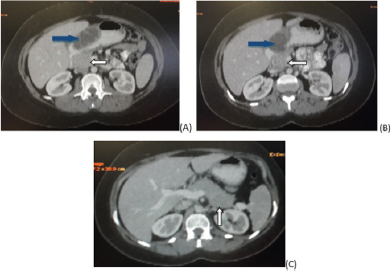

A 26 year old female presented in outpatient clinic during her second trimester of pregnancy with complaints of daily regular epigastric pain with off and on vomiting. The pain started during pregnancy 2 months back. She never felt such pain before. No melena or hematemesis. Thinking of peptic ulcer she was given proton pump inhibitors which showed no response. Ultrasound abdomen performed was unremarkable. CT abdomen with oral and IV contrast was advised due to her persistent symptoms. Scan showed a large low attenutation soft tissue exophytic lesion with septations and cystic changes arising from the body and pylorus of stomach. No contrast enhancement noted. Considering its size and appearances probable diagnosis of gastrointestinal stromal tumor (GIST) was made (Figures 1- 3). Endoscopy done demonstrated sub mucosal origin of the lesion and hence biopsy was not taken. She was referred to surgery department where she had partial distal gastrectomy and gastrojejunal anastomotsis. Histopathology came out to be heterotrophic pancreatic rest rather than neoplastic lesion (Figures 4 & 5).

Figure 1: (A, B and C) Axial images of CT abdomen performed with IV and oral contrast shows exophytic cystic density lesion (blue arrows in A & B) arising from gastric body and pyloric region. Normal pancreas seen in these images (white arrows).